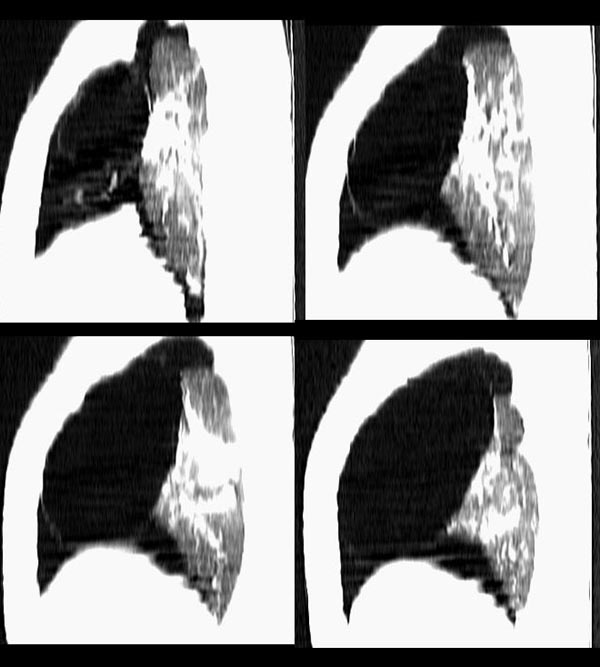

m21y既往体健,否认结核、支扩等病史;1周前患上感,无明显咳嗽,自觉无明显不适。单位体检透视时发现右侧液气胸!cr及ct如下(肺组织窗:l:-598hu w:1132hu):请大家会诊!!

本例病史无胸闷、气短等症状;影像学示气囊壁厚,病变区透亮度介于气胸与肺大皰之间,内无发丝样阴影,不伴有周围肺气肿;囊肿位于肺表面。壁厚,张力不高,在游离、切除过程中并不破裂,可与肺大皰相区别。另外,病人有长期吸烟史,每日30余支,术中却见肺表面如同正常小儿肺,无炭末、粉尘沉积,因此,该病可能为自幼存在的先天性疾病。

右侧巨大含气囊性病变,壁薄、光整、其外侧见气体。右肺压迫性肺不张、胸腔内见少量积液。纵隔向左侧移位。左肺未见异常。诊断:1.右侧含气肺囊肿(先天性)。2.右侧液气胸。(少量液体)3.右肺压迫性肺不张。我也遇见一例这样的病人。女性。股骨外伤就诊。常规胸片发现右侧囊性病变。